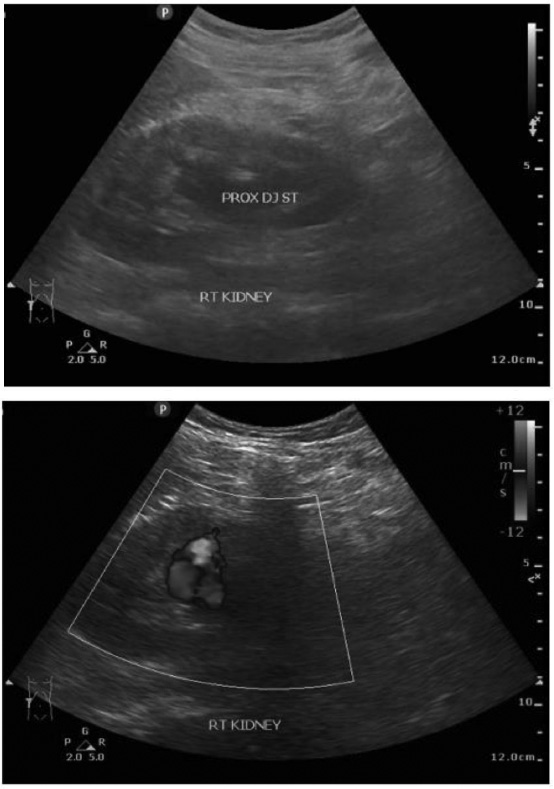

Fig. (1).

Pre-embolization ultrasound showing a decrease in vascularization in the right kidney with moderate hydronephrosis.

Fig. (3).

Ultrasound image post embolization with recurrent hematuria.

The Doppler ultrasound showed decreased vascularization in the right kidney with mild hydronephrosis (Fig. 1). Based on the symptoms, the team suspected a renal arteriovenous fistula and proceeded with renal embolization without prior CT angiography.

Three weeks post-procedure, the patient returned with severe hematuria and anemia. The physical evaluation during hospitalization revealed no abnormalities in the lung, cardiac, or limb examinations and the vital signs. The laboratory result of the erythrocyte was 2.75 × 10^6/uL, with the leukocyte value recorded at 7.4 × 10^3/uL and hemoglobin measured at 7.5 g/dL, urea levels at 12.0 mg/dL, and serum creatinine concentration at 1.6 mg/dL. The outcomes of all subsequent tests exhibited normal findings, including bleeding time, blood coagulation time, and plasma electrolytes. We assessed the patient for recurrent hematuria and a suspected pseudoaneurysm in the right renal artery. The patient underwent an ultrasound examination, which showed two-way flow with a “yin-yang sign” that could be a pseudoaneurysm in the right kidney and moderate hydronephrosis in the right kidney with a DJ stent in situ (Fig. 3). Due to recurrent hematuria, we conducted a second angiography and embolization again without prior CT angiography.